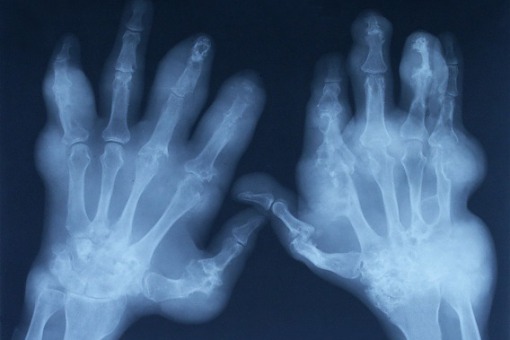

Inhibitory kinazy janusowej (JAK) to nowa grupa leków która jest wykorzystywana w chorobach zapalnych.

Niedawno opublikowano przegląd systematyczny z meta-analizą dotyczący profilu bezpieczeństwa tofacitinibu, upadacitinibu, filgotinibu i baricitinibu u pacjentów z reumatoidalnym zapaleniem stawów, chorobami zapalnymi jelit, łuszczycą oraz zesztywniającym zapaleniem stawów kręgosłupa.